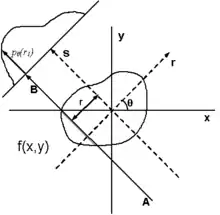

The projection of an object, resulting from the tomographic measurement process at a given angle , is made up of a set of line integrals (see Fig. 1). A set of many such projections under different angles organized in 2D is called sinogram (see Fig. 3). In X-ray CT, the line integral represents the total attenuation of the beam of x-rays as it travels in a straight line through the object. As mentioned above, the resulting image is a 2D (or 3D) model of the attenuation coefficient. That is, we wish to find the image . The simplest and easiest way to visualise the method of scanning is the system of parallel projection, as used in the first scanners. For this discussion we consider the data to be collected as a series of parallel rays, at position , across a projection at angle . This is repeated for various angles. Attenuation occurs exponentially in tissue:

Using the coordinate system of Figure 1, the value of onto which the point will be projected at angle is given by: